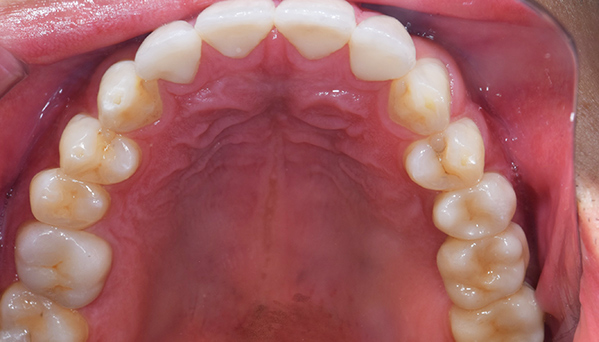

奥歯の詰め物の治療終了後

奥歯の治療が終わったところです。前歯の治療に行く前に、噛み合わせをしっかり確認します。

全ての治療終了後

前歯の治療が終わったところです。前歯は全く違和感がなく入っています。

全体の治療前後

銀歯の主張がなくなり、とても自然になりました。見た目もそうですが、雰囲気や第一印象もかなり変わりました。